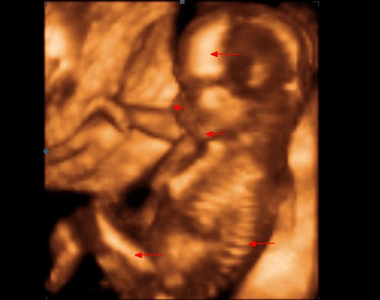

15. týden těhotenství pokračuje rychlý růst tělíčka plodu do délky. Na konci 4. měsíce tvoří hlavička asi třetinu celkové délky plodu. Mozek pokračuje ve svém vývoji. Na jeho povrchu se již vytvořila tenká vrstvička šedé hmoty.

Na povrchu hlavičky začíná být patrná část porostlá vlasy. Na okrajích očních víček se objevují jemné řasy. Oční víčka jsou stále srostlá.

Boltec ouška má už v podstatě definitivní tvar.

Celé tělíčko je pokryté velmi tenkou pokožkou. Jsou v ní již založeny všechny obvyklé vrstvy. Objevují se první buňky, které obsahují pigment. Jejich množení patří k faktorům, které v budoucnu ovlivní zbarvení kůže. Celý povrch těla je pokryt velmi jemnými kožními chloupky (lanugo).

V 15. týdnu těhotenství plod měří od temene k zadečku 9 - 10 cm, váží asi 40 – 50 g.